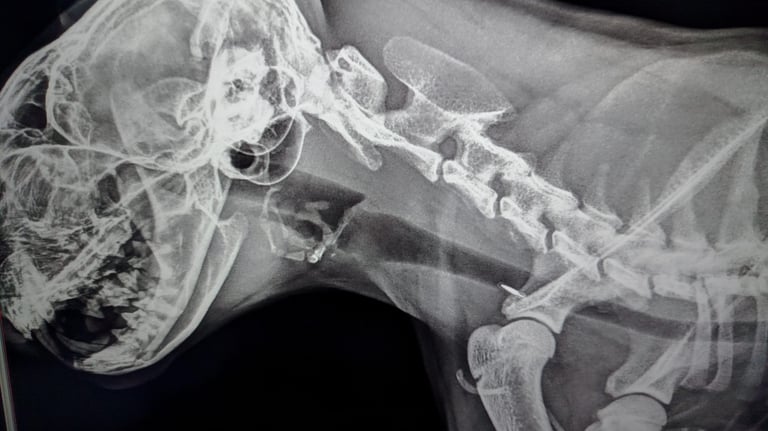

Radiología

Resultados inmediatos en pantalla: diagnóstico óseo y torácico al instante y en tu puerta